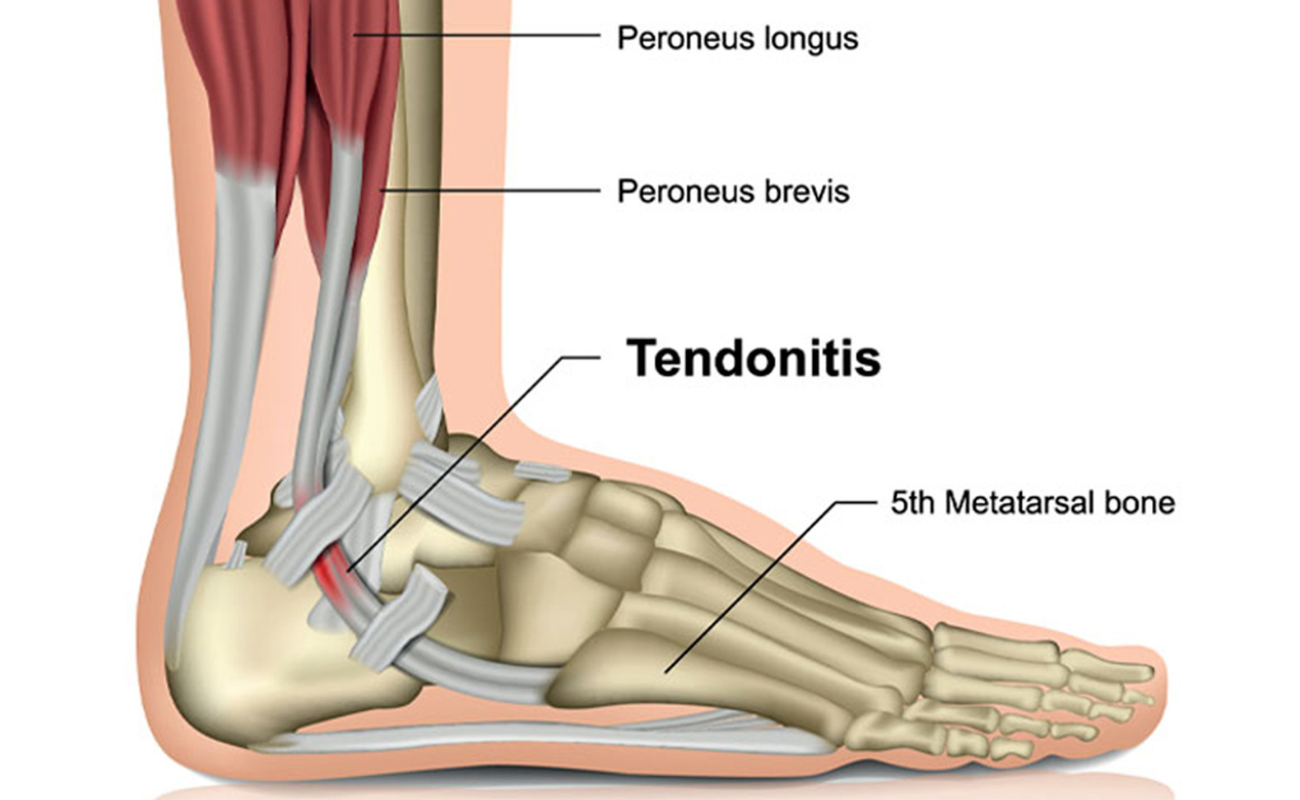

Tendonitis

Tendons connect bone to muscles. Tendonitis or Tendinitis is an inflammation or irritation of a tendon. This may be caused by any repetitive action such as gardening, carpentry, tennis etc. It could also be caused by a sudden injury.